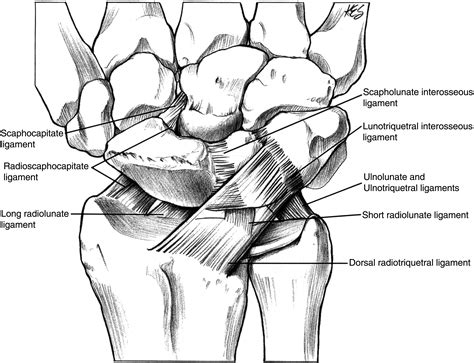

Understanding the Scapholunate Ligament

The scapholunate ligament is a critical structure in the wrist that provides stability and allows for smooth movement. It connects the scaphoid bone (a small bone on the thumb side of the wrist) and the lunate bone (a bone in the center of the wrist). This ligament is essential for maintaining the alignment of the carpal bones and ensuring proper wrist function.